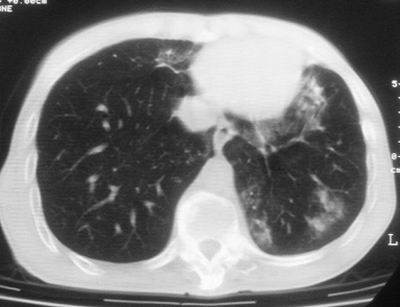

标题: CT11864:男,47岁,反复咳嗽、咯痰、咯血3年,请分析. [打印本页]

患者,男,47岁,反复咳嗽、咯痰、咯血3年,再发5天。痰培养未找到真菌、抗酸杆菌、癌细胞。

左肺上叶体积明显缩小,其内见多发透光区,纵隔向左侧移位,左肺下叶多发班片状病灶,边界模糊,1左肺上叶先天肺发育不全,2左肺下叶肺炎,

左肺上叶结核伴肺纤维化,纵隔移位,左肺下叶感染性病变,建议抗炎抗结核后复查,双肺气肿.

以下是引用xulianj在2008-2-25 21:01:00的发言:[br]左肺上叶结核伴肺纤维化有霉菌球形成,纵隔移位,左肺下叶感染性病变,建议抗炎抗结核后复查,双肺气肿.

考虑:左肺慢纤伴霉菌球形成、双肺全小叶型肺气肿。

1)考虑为:左肺上叶肺结核(空洞形成),伴左下肺感染;不排除霉菌感染可能。2)肺气肿。

左肺上叶结核伴肺纤维化空洞形成并左肺下叶感染,纵隔牵拉移位,建议作进一步检查排除左侧肺霉菌感染可能。